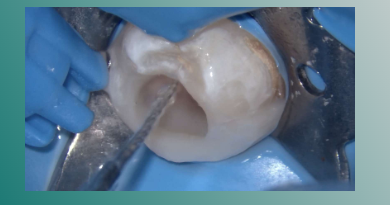

欧罗德卡U系列序列锉17045预备各根管,避免向舌侧刷壁。

欧罗德卡U系列序列锉22055预备各根管,避免向舌侧刷壁。

欧罗德卡U系列序列锉2506预备各报管,避免向舌侧刷壁。

欧罗德卡大号锉3504预备各根管,为主尖锉。

3%次氯酸钠大量冲洗根管,超声活化次氨酸钠,可见液体逐渐浑浊。

每根管间断活化20s,置换新鲜冲洗液2ml,重复三次。

T7%EDTA冲洗报管,超声活化EDTA。

蒸馏水超声荡洗

机械化学预备后

吸潮纸尖干燥根管

根管内注入氢氧化钙糊剂

髓腔内放置一无菌小棉球,蓝色玻璃离子暂封。